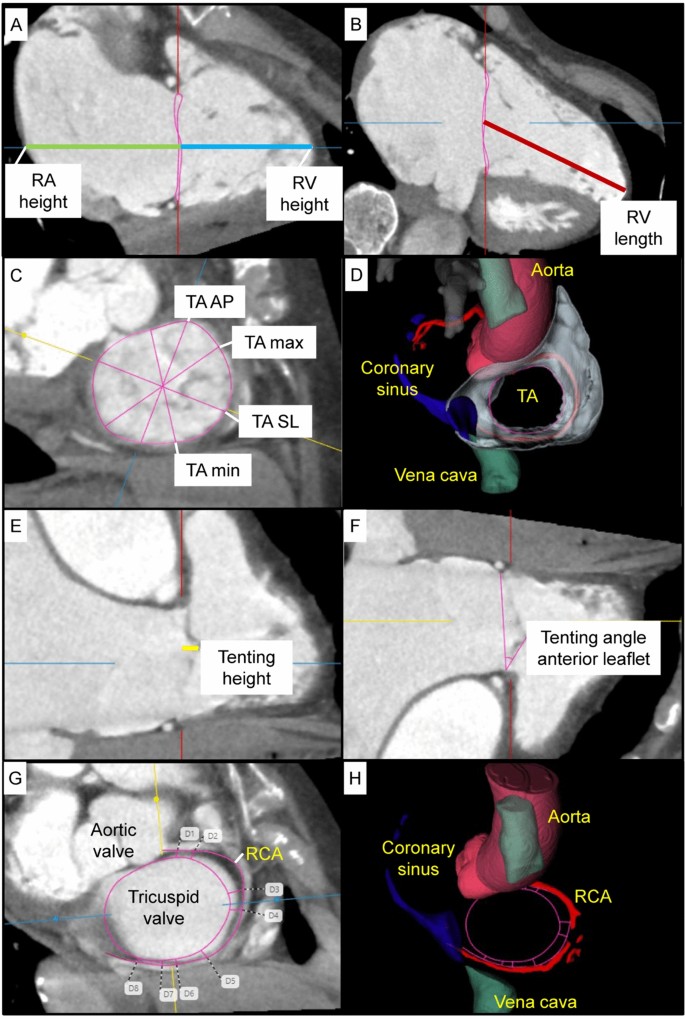

CT was performed before intervention during the screening process for TR therapy according to current recommendations20,21. For further analysis of the CTs, we used heart.ai version 1 (Laralab GmbH, Munich, Germany), a cloud-based software platform providing automatic analysis of cardiac CT images for research use (https://research.heartai-medical.com/). Heart.ai's computer modeling and simulation methods are based on deep learning techniques. Blood cavities and tissues of the heart were segmented using Convolutional Neural Networks, with different networks focusing on different groups of heart anatomies. The result was a comprehensive segmentation that included the major structures such as the left and right ventricles, as well as finer structures such as tricuspid leaflets. Segmentation was performed for each phase in a cardiac CT series, resulting in a detailed representation of the cardiac anatomy. 3D models of cardiac anatomy were produced from the binary masks of the segmentations using the flying edges algorithm22. Characteristic heart planes for multiplanar reconstruction views were calculated based on the 3D models, and custom algorithms were used to automatically derive a wide range of measurements, including annulus and right heart dimensions. The 3D models from a given CT series were collated to calculate phase-independent measurements, such as RV stroke volume. Furthermore, this allowed for 4D visualization of the heart's structural dynamics over the cardiac cycle. Automated cardiac CT analysis included the evaluation of right heart morphology and function, as well as TR measurements. Right atrial morphology was measured at the end-systolic phase, right ventricular morphology at end-diastolic phase, tricuspid annulus morphology at both end-systolic and mid-diastolic phases, and tenting parameters at the end-systolic phase. Manual adjustments were made if necessary. Tenting height as well as angles were measured by hand.

CT parameters are presented in Table 2 and shown in Fig. 2. Right ventricular and atrial volumes were increased in the PA compared to the T-TEER group, but these differences did not reach statistical significance. This was consistent with a more pronounced tenting in PA patients, including the tenting angle of the septal leaflet, which was significantly larger in the PA compared to the T-TEER group. The tricuspid valve area and diameters did not differ significantly between the two groups. The distance between the tricuspid annulus and the RCA was larger in patients who underwent PA compared to T-TEER with a significant difference in segment D8 (Fig. 2). 35 patients in the PA (67%) and 23 patients in the T-TEER group (72%) had at least one segment with a distance to the RCA < 6 mm.

Computed tomography (CT) analysis of right atrial (RA) and right ventricular (RV) height (A), RV length (B), tricuspid annulus (TA) with antero-posterior (AP), septo-lateral (SL), minimal (min) and maximal (max) diameter (C, D), tenting height (E), tenting angle of the anterior leaflet (F), and distance between tricuspid annulus and right coronary artery (RCA, G, H).

Technical success was achieved in 100% of patients. After interventional therapy, PA and T-TEER patients showed a comparable improvement of TR severity (PA: 2.3 ± 0.8 vs. T-TEER: 2.3 ± 0.9, p = 0.688). Detailed TR grades before and after intervention are shown in Fig. 3. For further analysis, we divided both treatment cohorts into patients with a TR grade ≤ 1 and > 1 after intervention. We observed that patients with a post-interventional TR grade ≤ 1 had smaller right ventricular volumes and lower tenting heights, volumes, and angles regardless of PA or T-TEER treatment. This difference reached significance only for tenting height and angles. A comparison of patients with a TR improvement of ≥ 3 grades and < 3 grades showed similar results, except for the right atrial diameter in the two-chamber view in the PA group (TR improvement of ≥ 3 grades: 102 (95–109) mm vs. TR improvement < 3 grades: 92 (83–100) mm, p = 0.019).

In the T-TEER group, the tenting height and the tenting angle of the anterior leaflet predicted a post-interventional TR grade ≤ 1 (tenting height: odds ratio [OR] 0.707 [95% confidence interval [CI] 0.537–0.931]; tenting angle: OR 0.919 [95% CI 0.850–0.993]). Neither right atrial volume, right ventricular end-systolic and end-diastolic volume, RVEF, tenting angle of the septal and posterior leaflet, tenting volume nor end-systolic and mid-diastolic tricuspid valve area as well as a more circular shape of the tricuspid annulus or the sphericity index predicted a TR grade ≤ 1 after T-TEER. Similarly, none of the mentioned parameters predicted a TR grade ≤ 1 after PA.

Furthermore, we conducted a ROC analysis with tenting height, volume, and angles to predict the outcome TR grade > 1 after intervention (Fig. 4). The tenting height showed the best diagnostic accuracy among evaluated parameters with an AUC of 0.756 (95% CI 0.560–0.951) in the T-TEER and 0.658 (95% CI 0.501–0.815) in the PA group. To determine post-interventional TR grade > 1, the threshold of 6.8 mm tenting height corresponded to a sensitivity of 83% and specificity of 70% in the T-TEER group, while the cut-off value of 9.2 mm was associated with a sensitivity and specificity of 68% in the PA group (Fig. 5).

CT and echocardiographic measurements showed a significant correlation regarding left ventricular ejection fraction (LVEF, Pearson 0.574, p < 0.001, n = 84), right atrial diameter in the four-chamber view (Pearson 0.619, p < 0.001, n = 84), right ventricular length (Spearman-Rho 0.648, p < 0.001, n = 83) and tenting height (Pearson 0.603, p < 0.001, n = 84). Echocardiographic parameters are listed in Table 3.